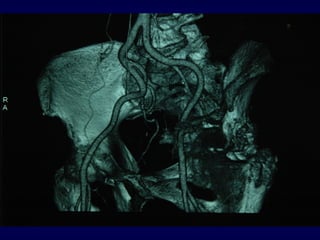

-Angiografia – Angio-TAC (2D – 3D)

-Rapporti anatomici alterati